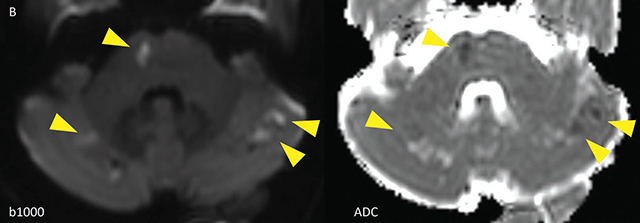

Teaching point: Meningovascular neurosyphilis is a cause of stroke in the young, and the diagnosis could be aided by black-blood MRI sequences.

教学要点:脑膜血管神经梅毒是导致年轻人中风的原因之一,黑血磁共振成像序列可以帮助诊断。